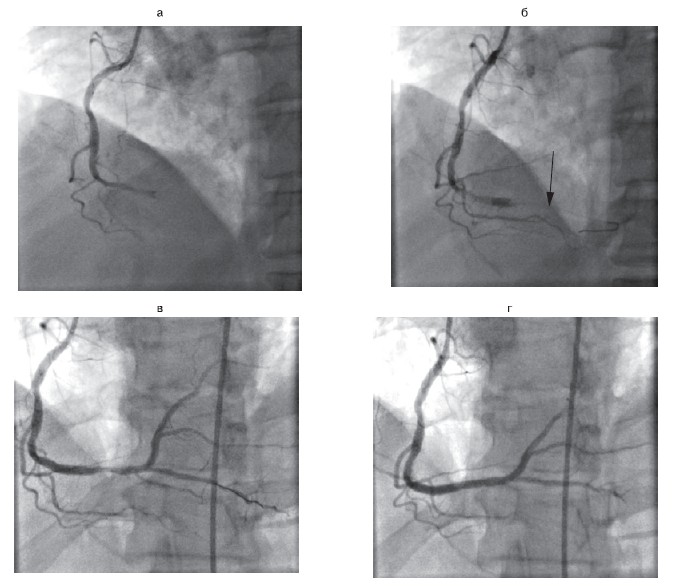

Рисунок 1. Пациент М., 37 лет. Диагноз: Q-негативный инфаркт миокарда передней стенки левого желудочка. Успешная реканализация и стентирование.

а — окклюзия в проксимальном отделе передней нисходящей артерии; б — результат после ЧТКА. Здесь и на рис. 2, 3: ЧТКА — чрескожная транслюминальная коронарная ангиопластика.

Рисунок 2.Пациент В., 43 года. Диагноз: ОКСпSТ. Успешная реканализация и стентирование.

а — окклюзия в проксимальном отделе огибающей артерии; б — результат после ЧТКА. OKCпST — острый коронарный синдром с подъемом сегмента ST.